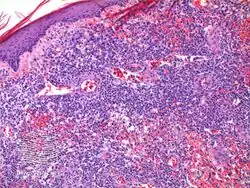

It has been described as "clinically benign but histologically malignant."[6]

Diagnosis of lymphomatoid papulosis is done via the presentation and a skin biopsy[7]